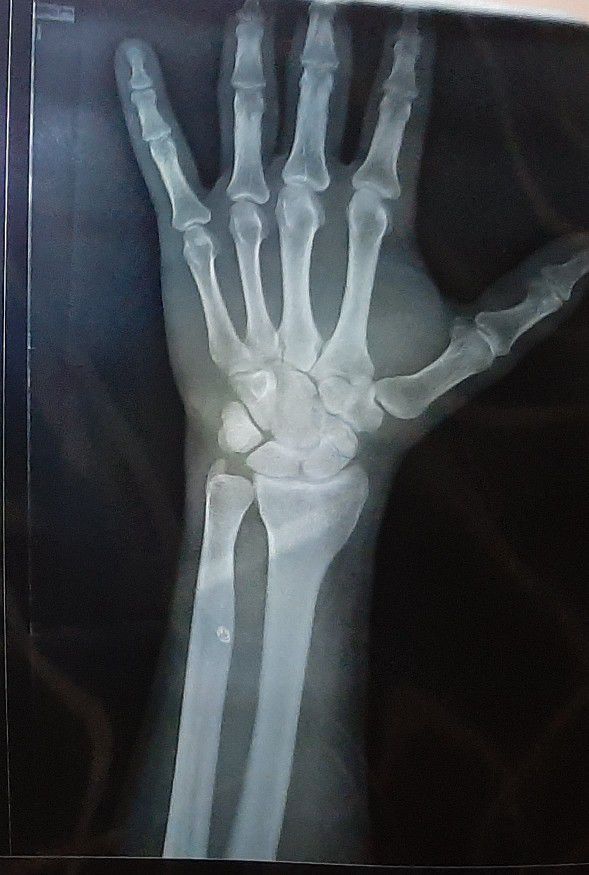

Your opinion ?

Fracture

Joint

Wrist